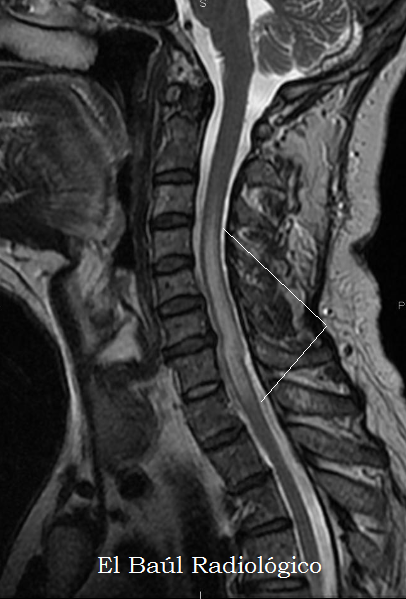

El Baul Radiologico Edema De La Medula Espinal Hallazgos En Irm Spinal Cord Oedema Mri Findings By Luis Mazas Artasona Octubre 16